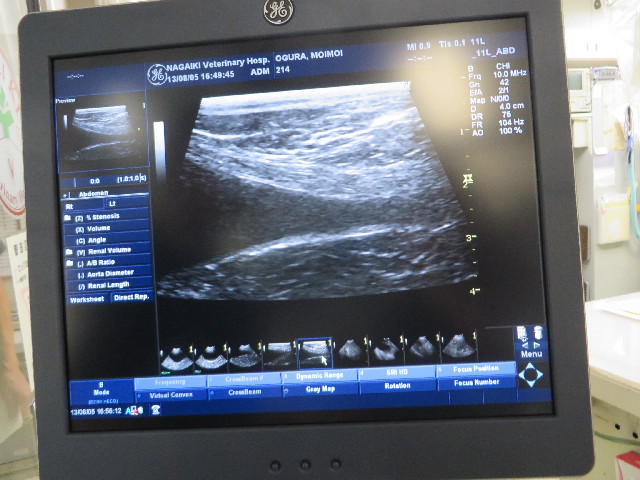

いよいよガンができやすい場所。

これは何か特殊な写し方だそうですが、大丈夫でした!!

ガンではありませんでした!!!!